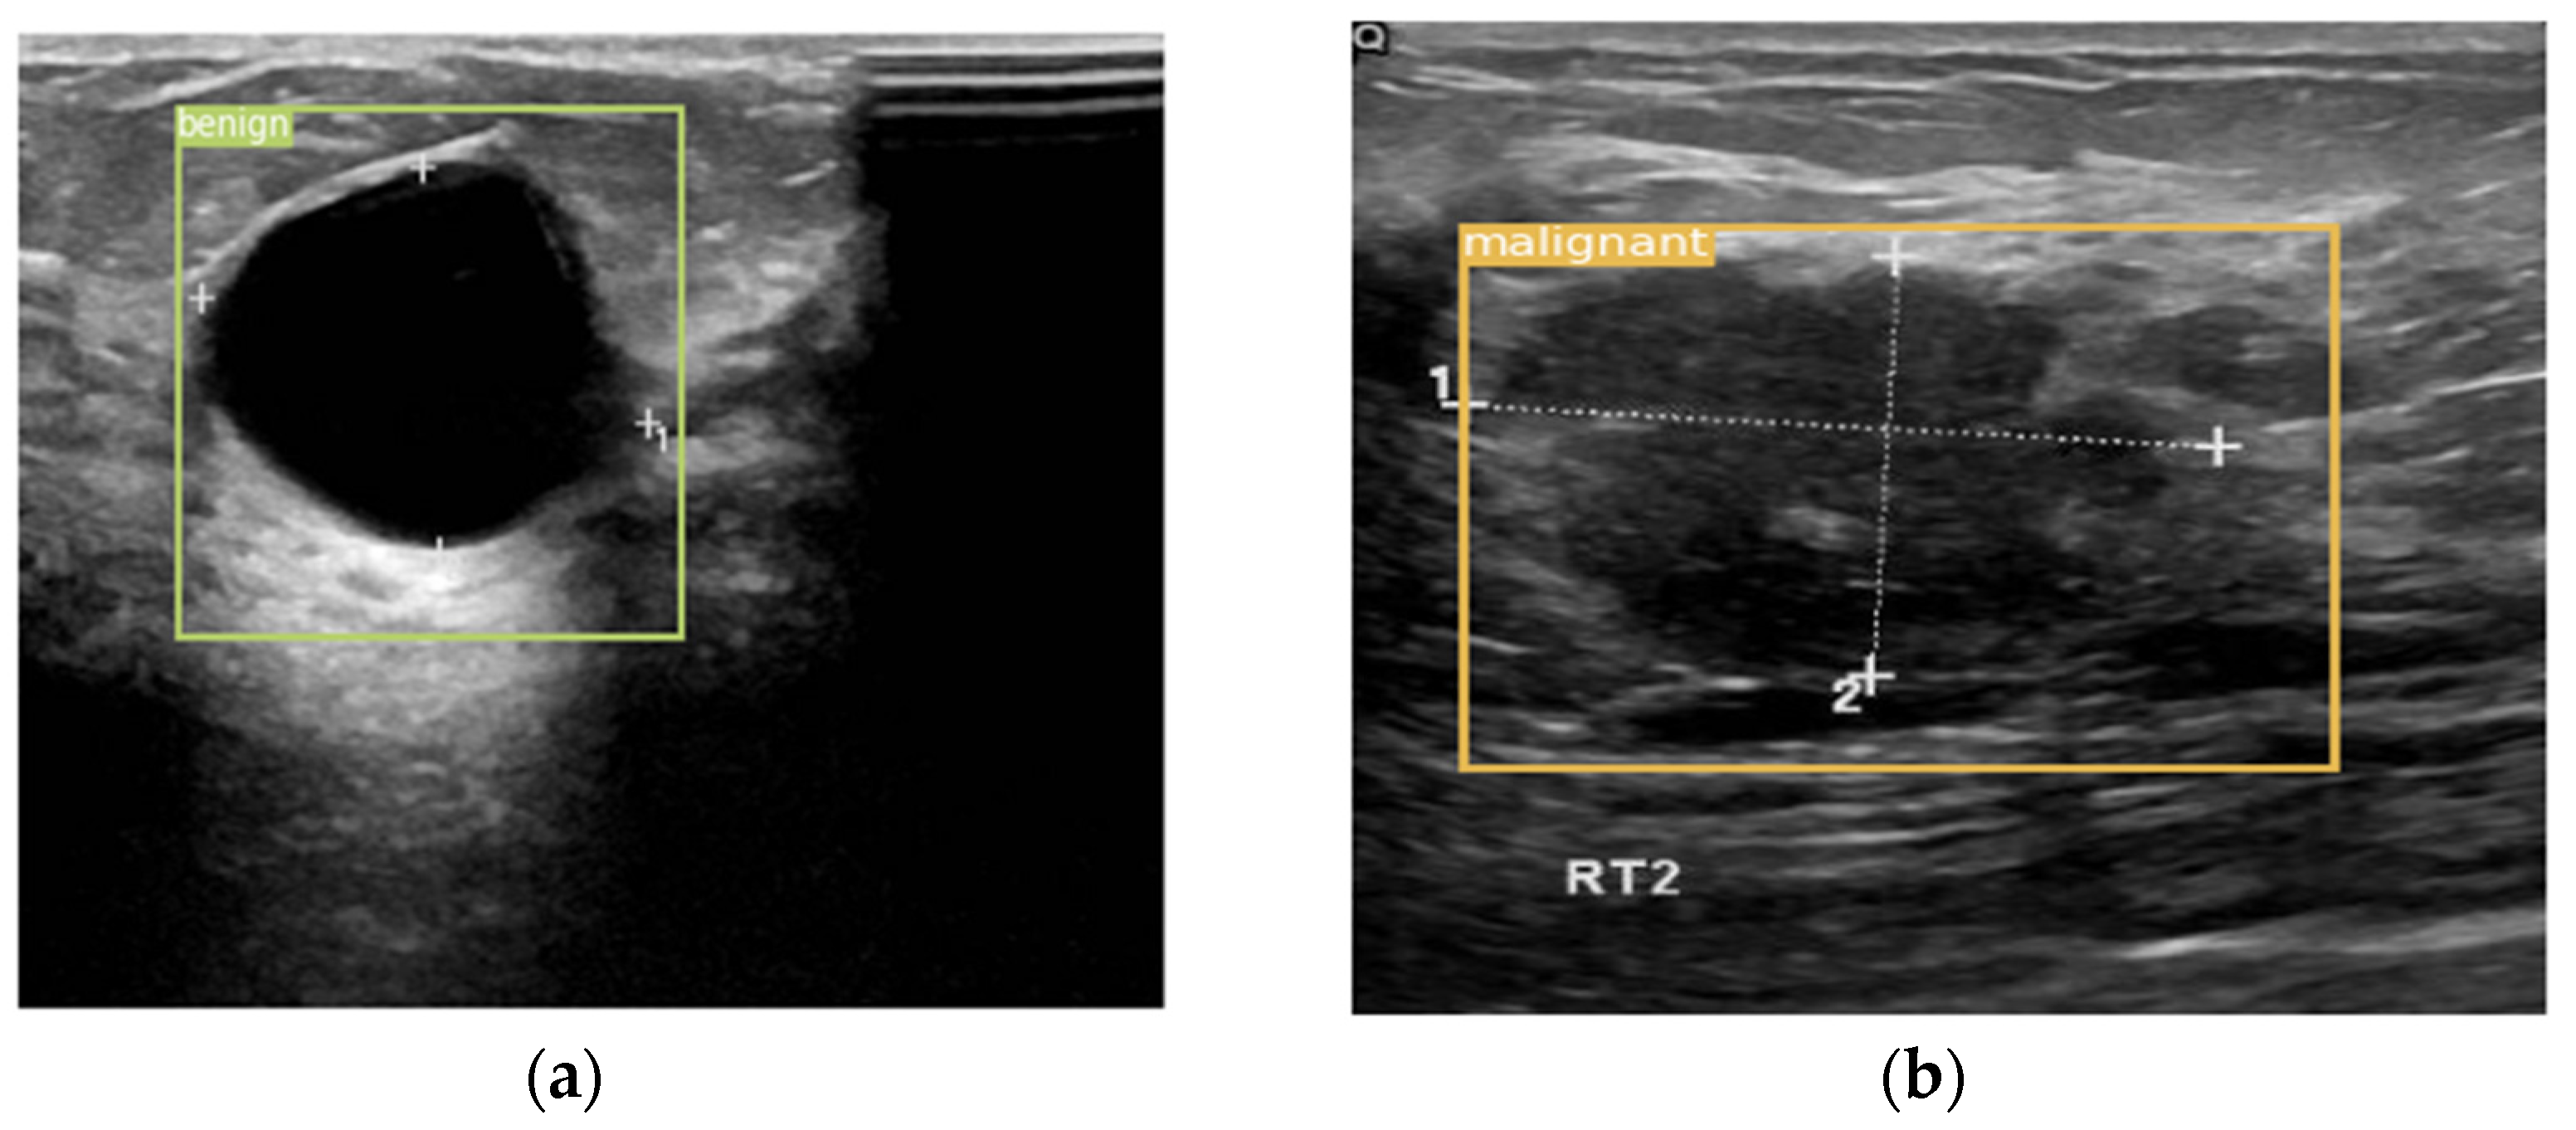

The datasets used in this work can be applied to the segmentation, classification, and detection of breast cancer. The data provides classification labels and segmentation labels. However, the datasets do not contain labels for object detection. Therefore, the labels are manually labeled using the open-source script LabelImg. An example of the annotated image is shown in Figure 9. Figure 9a is the annotation of malignant lesions in an ultrasound image, and Figure 9b is the annotation of benign lesions in the DDSM database.

Figure 10 is a schematic diagram of the detection results. Figure 10a is the detection result of a benign lesion, and Figure 10b is the detection result of a malignant lesion. The method proposed in this paper can accurately detect the type and location of the lesion on the breast ultrasound dataset.

Figure 9. An example of annotated image. (a) Annotation of malignant lesions in an ultrasound image. (b) Annotation of benign lesions in the DDSM database.

Figure 10. An example of a detection result. (a) The detection result for the benign lesion. (b) The detection result for the malignant lesion.